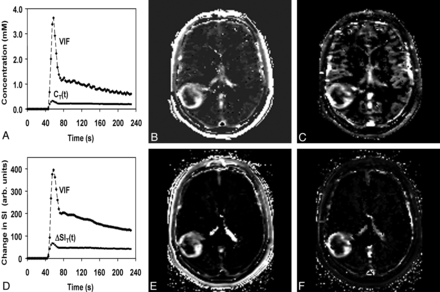

Voxel wise maps of CT(t) were calculated in 2 steps. First, the double echo was used to extrapolate all magnitude signals to TE = 0 ms, thereby reducing T2* effects. Second, the pre- and post-DCE T1 maps were combined with the extrapolated tissue signal-intensity-versus-time curve by using standard signal-intensity equations to compute CT(t). The VIF was calculated from the superior sagittal sinus by measuring the change in phase as a function of time, taking into account the angle of each vessel segment relative to the main magnetic field. This step was performed off-line by using in-house software written in IDL (ITT Visual Information Solutions, Boulder, Colorado) and is described in a previous article.8 Voxel-by-voxel estimates of Vp_ϕ and Ktrans_ϕ were determined by using a kinetic model analysis from the nordicICE software (Version 2; NordicNeuroLab, Bergen, Norway) as described in the Appendix. Representative parametric maps of Vp_ϕ and Ktrans_ϕ are shown in Fig 1B, -C.

A, Phase-derived VIF and tumor CT(t) from a patient with confirmed grade IV glioma obtained at 3T. B and C, Ktrans_ϕ (B) and Vp_ϕ (C) maps. D, Magnitude-derived VIF and tumor signal-intensity changes from the same patient for comparison. E and F, Ktrans_SI (E) and Vp_SI (F) maps. Maximal Ktrans_ϕ and Vp_ϕ values in tumor are 0.099 minutes−1 and 5.7 mL/100 g compared with 0.15 minutes−1 and 18 mL/100 g for Ktrans_SI and Vp_SI.

DCE magnitude images were processed directly in Nordic ICE to generate maps of Vp_SI and Ktrans_SI as described in the Appendix (Fig 1D, -E).